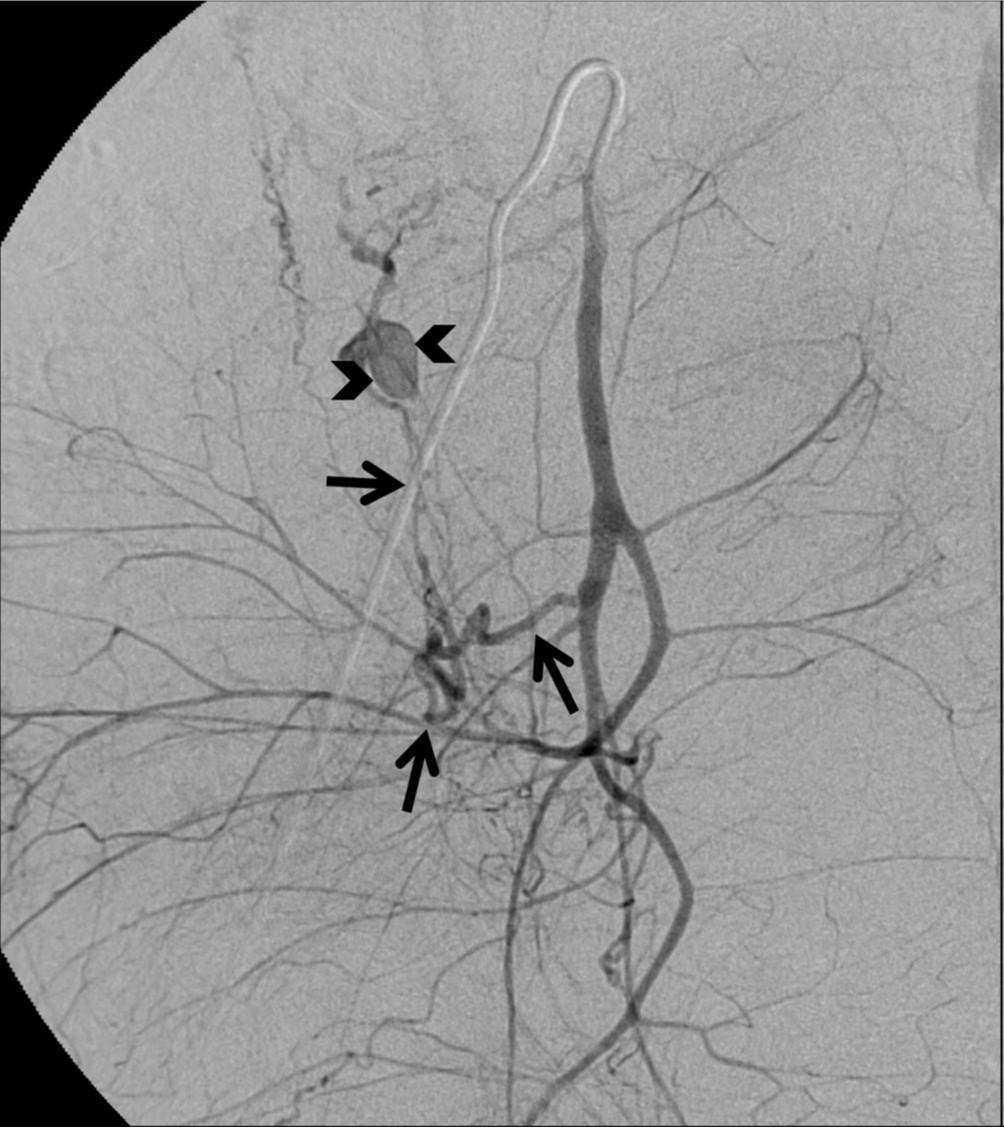

Fig. 3.

Pseudoaneurysm in the right uterine artery is no longer seen on the right internal iliac angiogram after embolization.